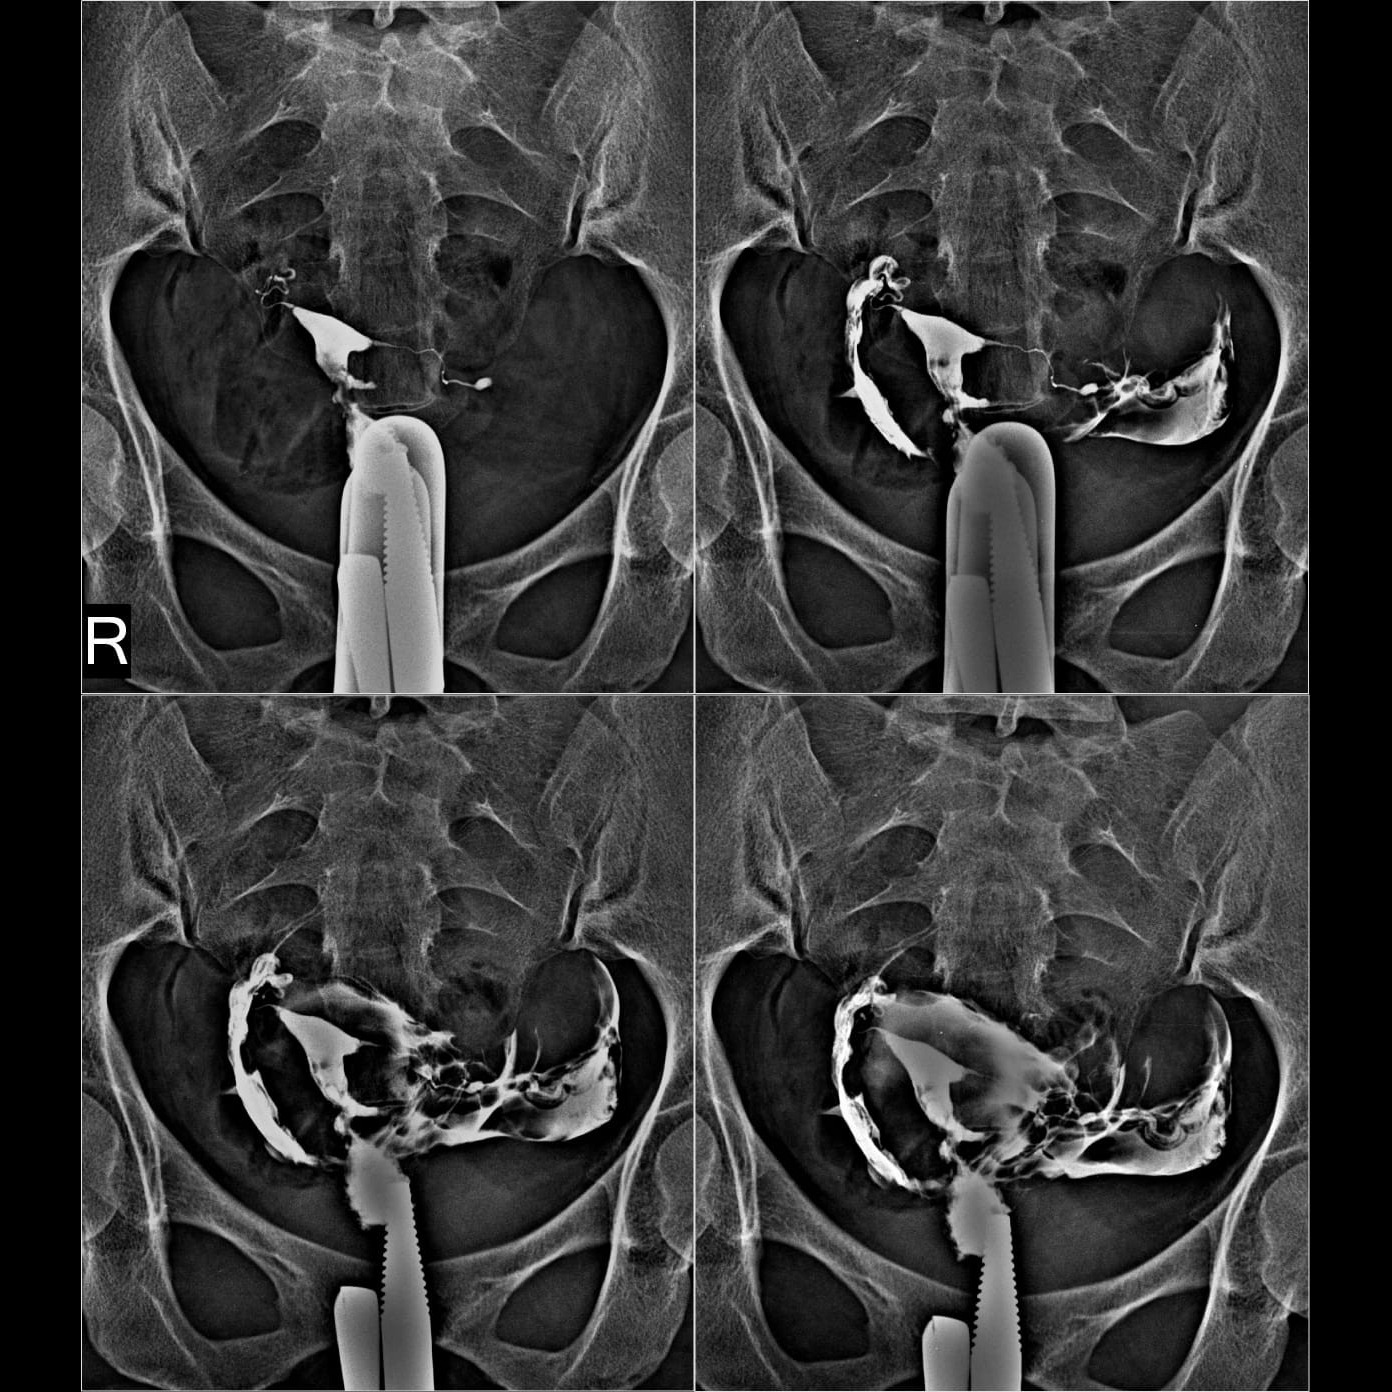

HSG (hysterosalpinogram)